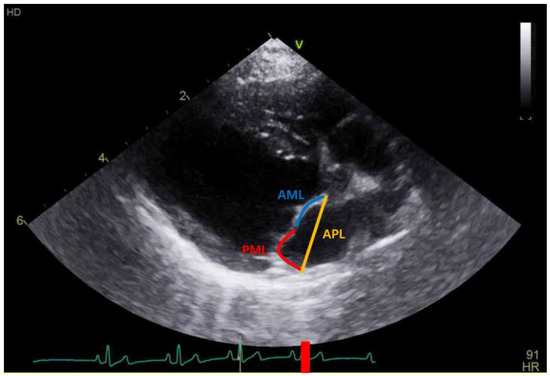

| APL (mm) | 15.15 (13.09–17.55) | 16.74 (15.08–18.23) | 19.89 (17.45–22.54) | <0.001 | a,b < c α,δ,ε |

| LAI | 1.27 (1.21–1.37) | 1.14 (1.10–1.20) | 1.07 (1.05–1.14) | <0.001 | c < b < a β,γ,ε |

| LAI | −0.367 ** | −0.356 ** | −0.432 ** | −0.334 ** | −0.392 ** |